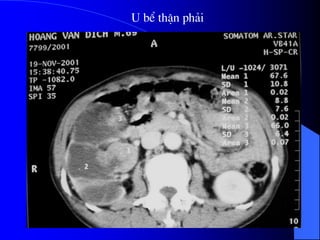

4. U hãûtiãút niãûu Vãö màût tãú baìo, ngæåìi ta xãúp u biãøu mä tháûn vaì u khäng do biãøu mä tháûn. - Carrcinome biãøu mä tháûn aïc tênh chiãúm 85% caïc loaûi u tháûn ngæåìi låïn. - U biãøu mä tháûn laình tênh ráút hiãúm gàûp, gäöm adeïnome, oncocytome, nephrome kystique. - U khäng do biãøu mä tháûn laì u maûch - cå - måî (angiomyolipome) laình tênh. Caïc loaûi khaïc hiãúm gàûp: u måî, u maïu, u baûch maûch, sarcome xå, sarcome måî, sarcome cå...

ÅÍ treí em,u aïc tênh cuía tháûn laì u nguyãn baìo tháûn (u Wilms), hay gàûp nháút trong caïc u äø buûng åí treí nhoí 1-8 tuäøi (> 90%), chiãúm 12% trong säú caïc u aïc tênh cuía tháûn åí moüi læïa tuäøi noïi chung. - U thæåìng låïn 3-25cm, coï khi chiãúm 1/3 troüng læåüng treí. - Thaình pháön bãn trong u gäöm caïc täø chæïc hoaûi tæí, xuáút huyãút, keïn vaì täø chæïc xå.

• 77.

- Lám saìng:âaïi maïu (50%), âau læng, såì tháúy khäúi, säút dai dàóng hoàûc nhæîng dáúu hiãûu do u tháûn âaî di càn. hoàûc khäúi u tháûn coï thãø âæåüc phaït hiãûn tçnh cåì trãn siãu ám hoàûc CLVT, Siãu ám laì phæång tiãûn phaït hiãûn thäng duûng âäúi våïi nhæîng khäúi åí tháûn. CLVT là KT để xác định - Âaïnh giaï lan räüng cuía u phaíi cáön CLVT. - NÂTM chè âãø khaïm xeït âæåìng dáùn niãûu bë xám láún, nhæng chè cáön chuûp 1-2 phim ngay sau chuûp CLVT coï tiãm TCQ (uro - scanner). - CHT âæåüc daình cho nhæîng bãûnh nhán dë æïng Iode, xem xeït nang xuáút huyãút, âaïnh giaï xám láún ténh maûch.

• 78.